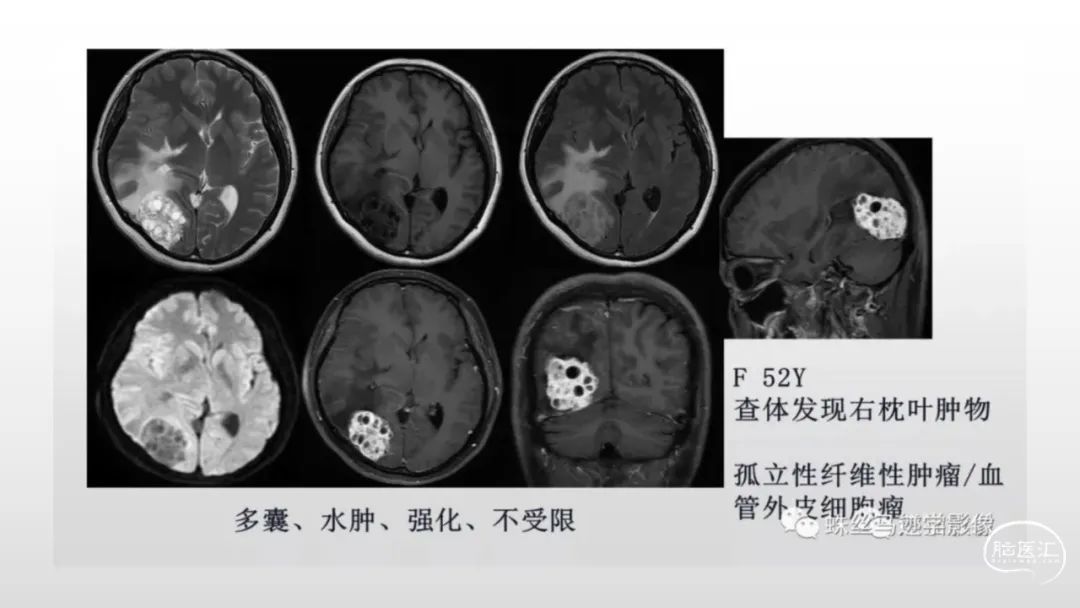

颅脑影像诊断基础知识讲座:脑膜病变